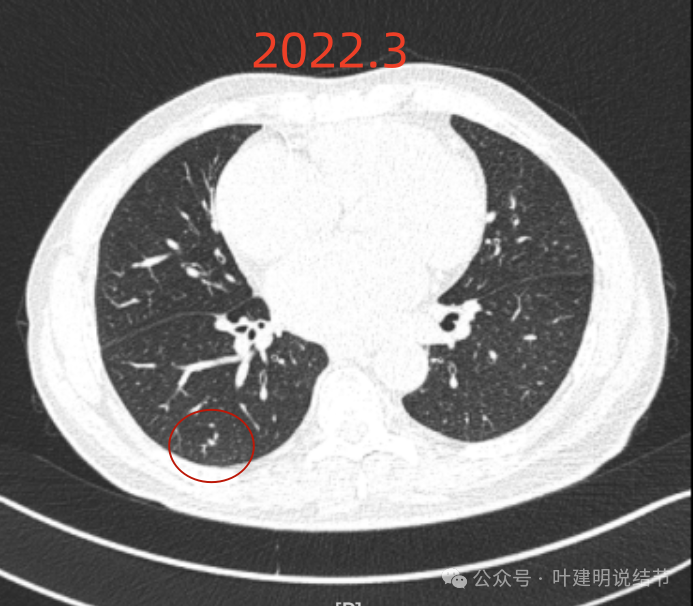

再看2022年8月复查时AI报告找出来的影像:

多是微小实性结节,主要的仍是右上与左下的这两处,较3月时无明显变化。而右下原来似有微小结节处这次并不明显。